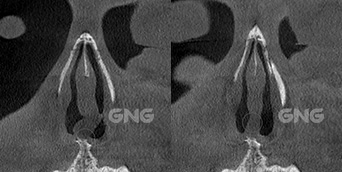

왼쪽 코의 코막힘 증상으로내원해주신 분입니다.코막힘 원인을 파악하기 위해 3D-CT를 촬영했는데요.아래 사진들을 보시면 비중격 만곡증 증상인휘어진 비중격의 모습을 육안으로 확인할 수 있습니다. 왼쪽에 뼈가 많이 튀어나와있고수술 후 해당 위치의 뼈가 제거되면서양쪽 비강, 특히 좁았던 왼쪽 부분이열린 모습을 볼 수 있습니다. <코막힘 원인> 수술 전, . . .